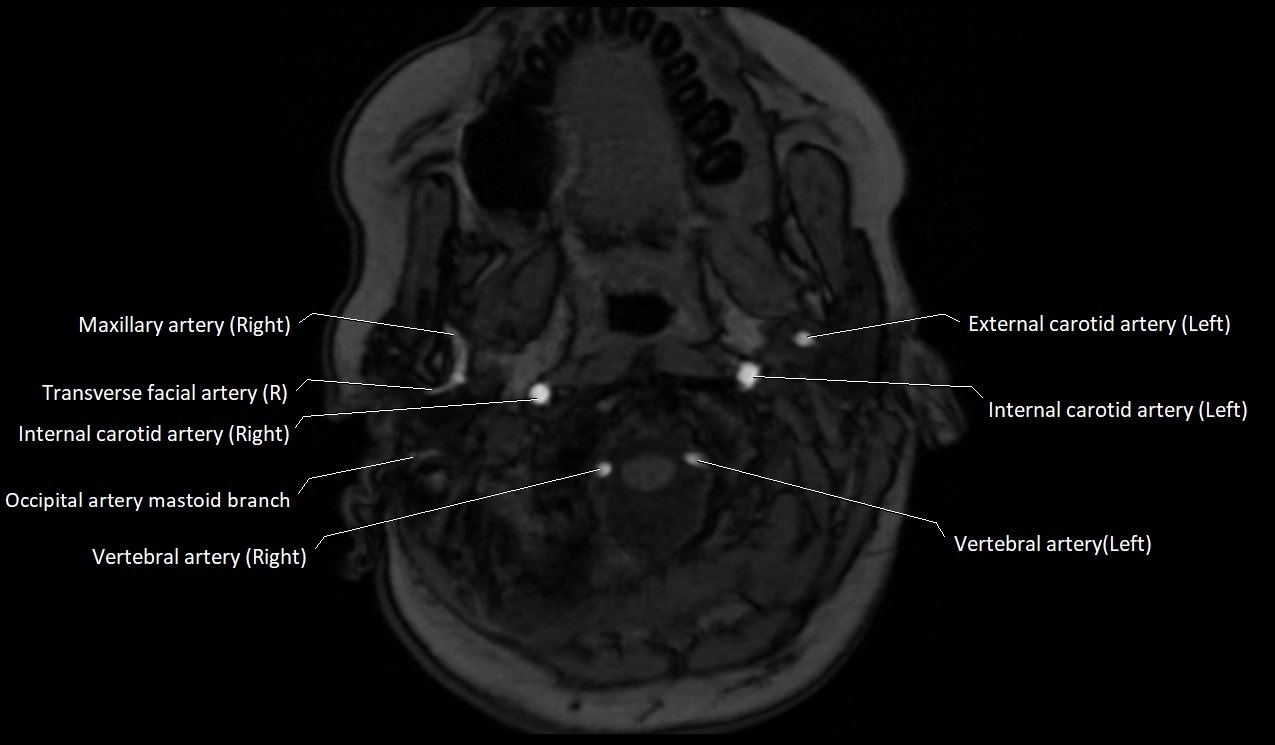

MRI images

image